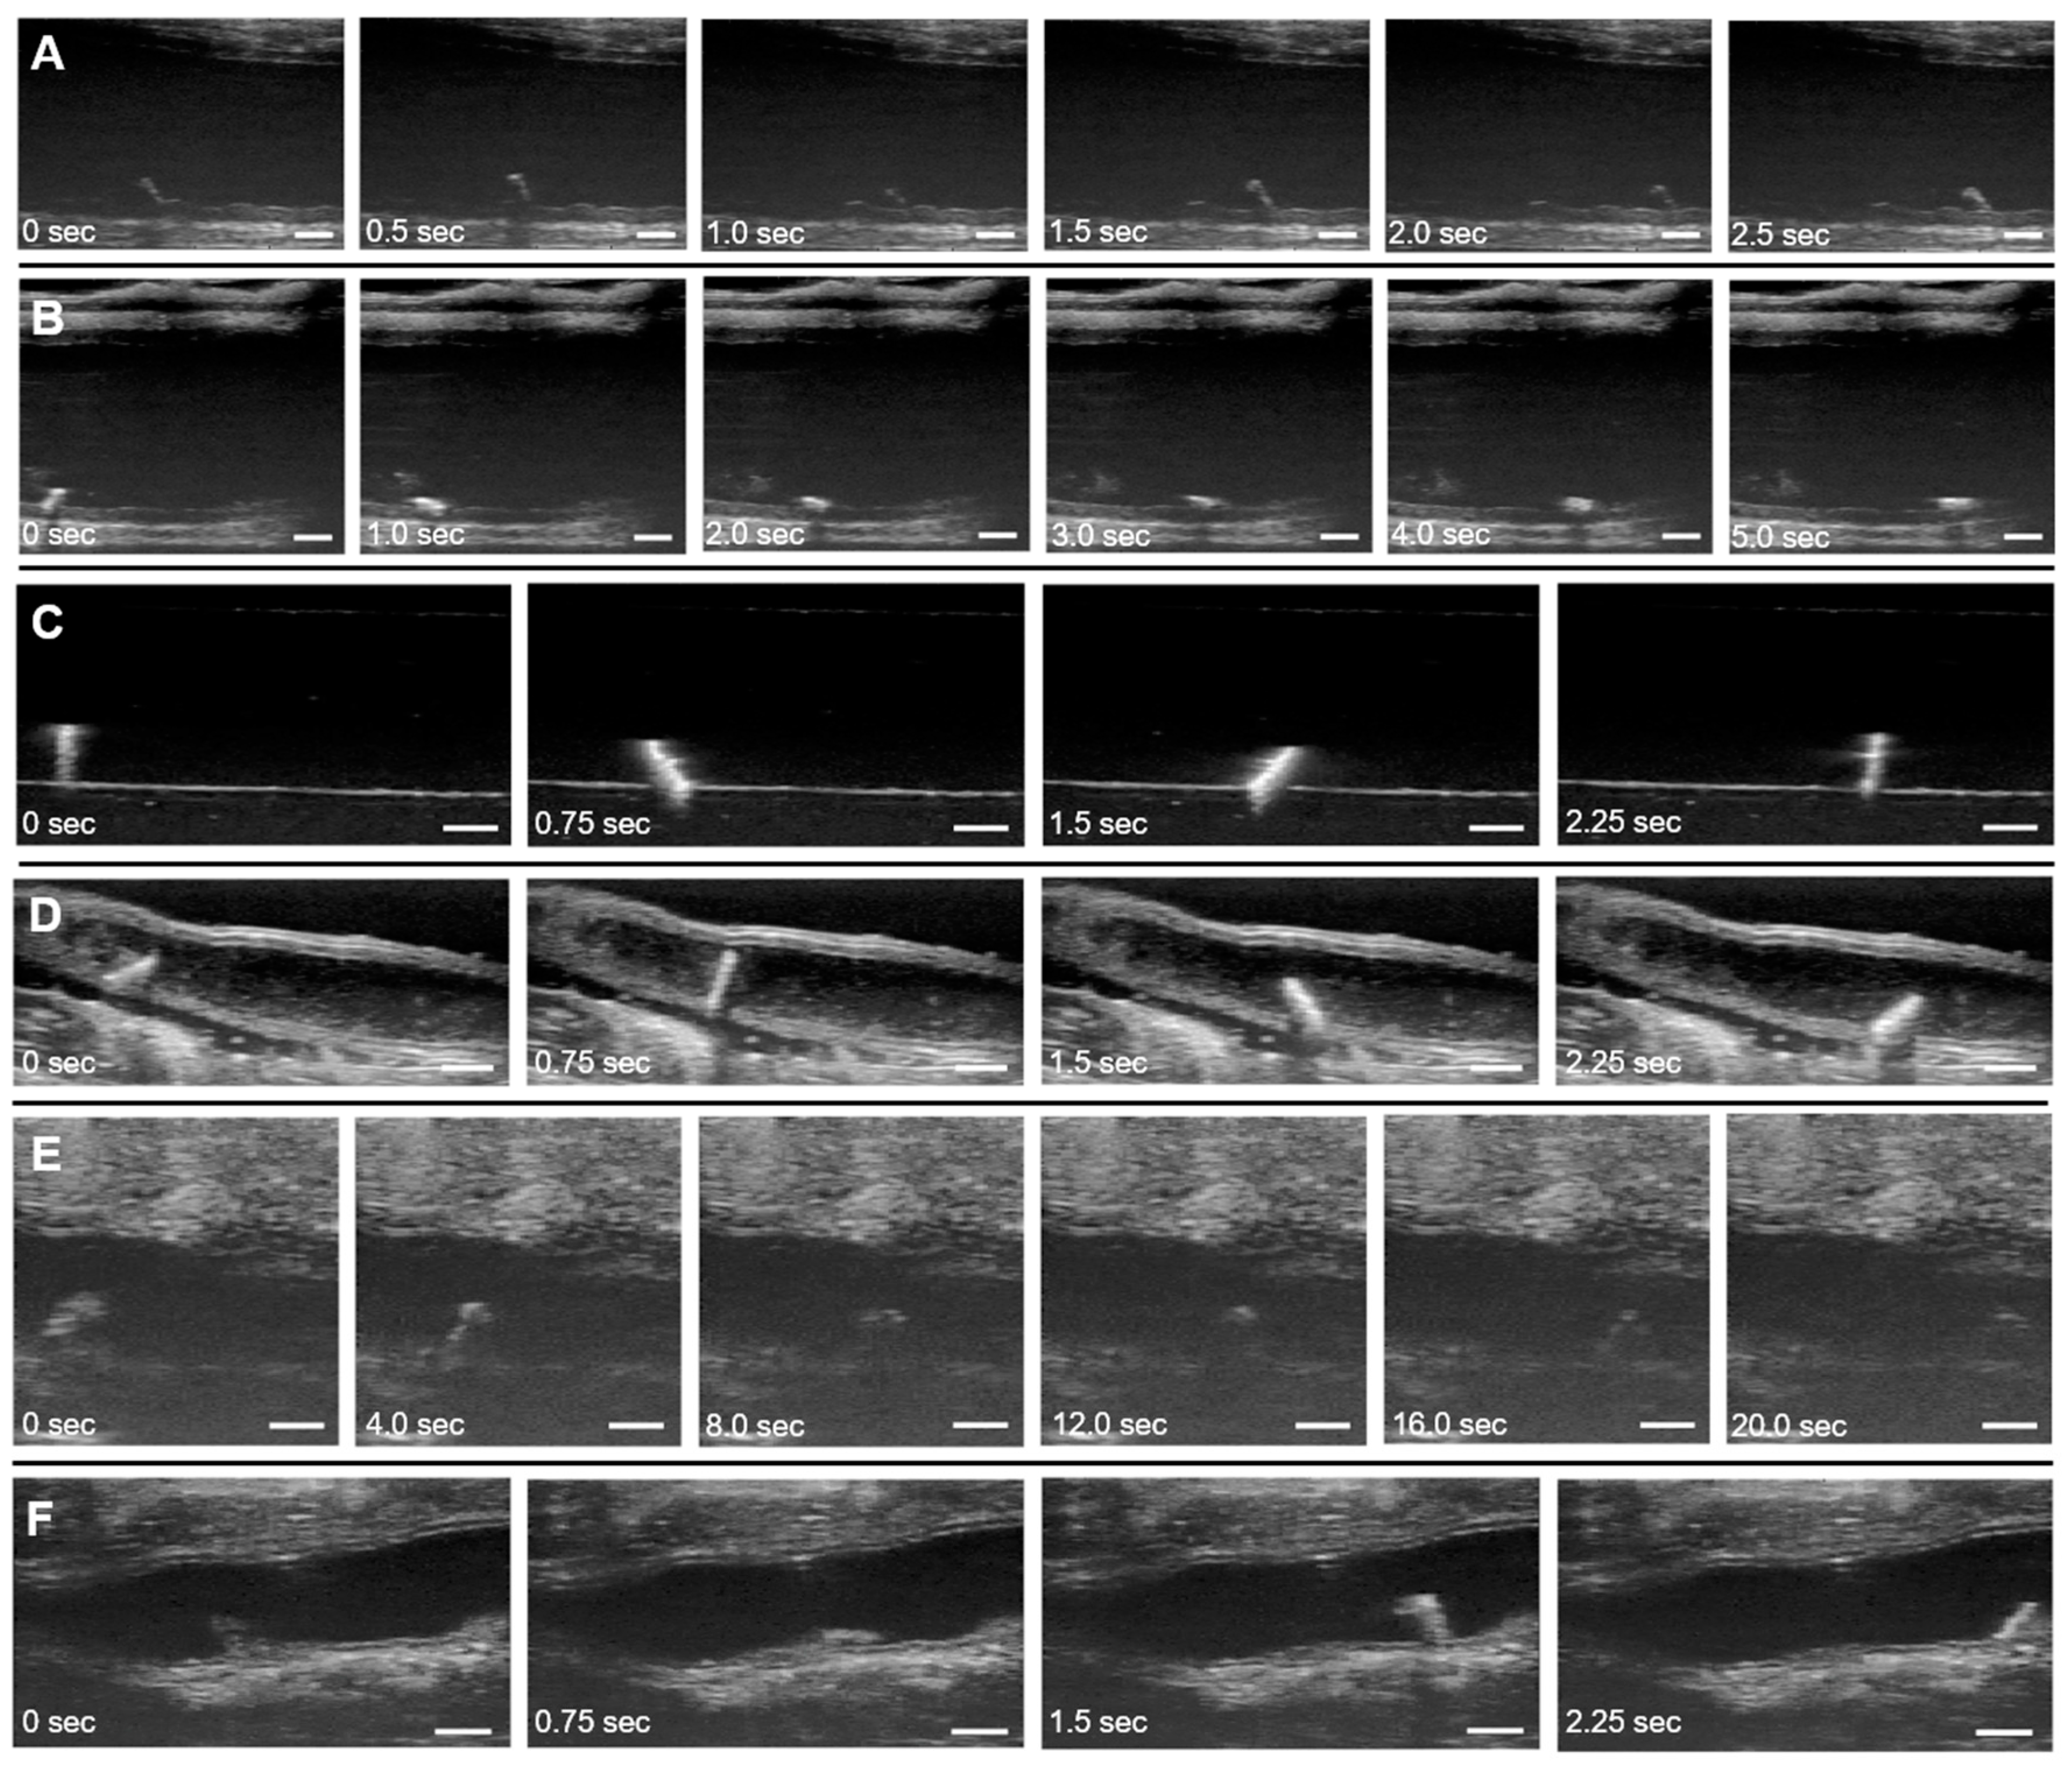

All tested microrobots were able to move laterally across the colon at magnet rotation frequencies of 0.5, 1.0, and 1.5 Hz. Figure 5A,B shows the SU-8 lengthwise microrobot moving under a rotation frequency of 1.0 Hz in the ex vivo porcine conditions. More than one microrobot can also move and be imaged within the colon at a time (Movie S1). Increased magnet rotation frequency resulted in an increase in the translational velocity of the microrobots in a roughly linear relationship (Figure S8). Table 1 lists the average velocities of the four microrobot variants across six trials for each rotation frequency. Trials were further organized based on the direction of the tumbling motion (forwards or backwards) due to its impact on the resulting microrobot velocity between each trial. Additionally, the previous microrobot is replaced with another one with the same design and a new starting location is used for each trial. A two-way ANOVA and the post hoc Tukey’s test were run on the data and showed significance between materials, PDMS vs. SU-8, as well as between the tumbling orientation, lengthwise vs. sideways [39,40]. These tests were ran using GraphPad Prism v. 8.1.0 (GraphPad Software). The lengthwise tumbling microrobot variants were found to be faster than the sideways tumbling variants, as expected, and the PDMS microrobots were found to be slower than their SU-8 counterparts. Due to the higher average translation speeds observed for the SU-8 lengthwise microrobots compared to the other microrobot variants, these microrobots were used for all subsequent testing.

Figure 5.

Real-time ultrasound B-Mode images of microrobots moving in ex vivo, in vitro, in situ, and in vivo conditions. Ultrasound images were analyzed using MATLAB (MathWorks, Natick, MA, USA) to incorporate a timestamp and larger scale bar while slowing down the frames to use for manual measurements. (A) SU-8 lengthwise microrobot moving in porcine colon in water (ex vivo). (B) SU-8 sideways microrobot moving in porcine colon in water (ex vivo). (C) SU-8 lengthwise microrobot moving in 1% agarose tunnel in water (in vitro). (D) SU-8 lengthwise microrobot moving in saline solution inside murine colon with tissue anterior to the colon removed (in situ dissected). (E) SU-8 lengthwise microrobot moving in intact colon of euthanized mouse in 1% Tylose solution (in situ intact). (F) SU-8 lengthwise microrobot moving in colon of live mouse in saline solution (in vivo). A magnet rotation frequency of 1 Hz was used in all of the images. Scale bars are 1 mm. (Movie S1 shows microrobot locomotion in porcine colon tests; Movie S2 shows microrobot locomotion in agarose and murine colon tests.).

3.3.2. In Vitro Locomotion

Figure 5C shows the microrobot traveling through a water-filled agarose tunnel. The 3.125 mm diameter tunnel was carved out of a 1% agarose (Thermo Fisher, Waltham, MA, USA) gel block, and the entire block was submersed in water over a glass dish, outside of any living organism (in vitro). Due to the uniformity of the agarose material and lack of complex tissues in this environment, the resultant ultrasound images showed the strong contrast between the microrobot and its surrounding environment.

3.3.3. In Situ Dissected Locomotion

In situ dissected tests were performed with the microrobot moving inside a colon from a euthanized C57BL/6 female apolipoprotein E (apoE−/−) knockout mouse at 12 weeks of age. The tissue anterior to the colon was removed and a microrobot was then placed inside the colon through the anus (Figure S9). The colon was filled retrograde with saline (0.9% sodium chloride, Hanna Pharmaceuticals) and long-axis ultrasound images of the mid and distal regions were acquired [36]. The colon tissue was sutured on both ends to contain the saline and ensure the colon walls would not collapse on the microrobots inside, which would restrict motion. Figure 5D shows images from one of these experiments.

3.3.4. In Situ Intact Locomotion

For the in situ intact test case, the colon of a euthanized knockout mouse was left intact and a microrobot was again inserted into the anus of the mouse. The colon was filled with a 1% Tylose solution (HS 100,000 YP2, Shin-Etsu, Tokyo, Japan) instead of saline or water (Figure S10). This solution was much more viscous than the latter fluids, which allowed it to support the shape of the colon without the need of other constructs, such as sutures, to prevent the walls from collapsing and limiting microrobot motion (Figure 5E). The microrobot could not rotate in solutions even more viscous than 1% Tylose, such as standard ultrasound gel.

3.3.5. In Vivo Locomotion

For the in vivo test case, the murine preparation procedure for colon imaging used by Freeling et al. was followed and is further detailed in the experimental section [36]. The colon was filled with saline instead of 1% Tylose and the fluid was contained inside the colon by placing a clothespin on the rectum. An atropine injection was also used to halt peristaltic contractions of the colon during the test. These steps resulted in a test environment more favorable for imaging and microrobot movement, with a less viscous medium and fewer time-varying disturbances. Figure 5F shows the microrobot locomotion for one of the in vivo tests.

The microrobot velocities in the in vitro, in situ, and in vivo conditions are recorded in Table 2. The magnet rotation frequency was kept at 1 Hz for all of these test conditions. Average velocities varied between the different conditions, reaching the highest magnitude in the aqueous in vitro tests and the lowest magnitude in the in situ intact tests in 1% Tylose. These differences are primarily due to the differing solution viscosities and terrains in each test environment. Table 3 shows the different viscosities that the SU-8 lengthwise microrobots were tested in with the microrobots being unable to move in ultrasound gel but having movement in other less viscous solutions. The 1% Tylose solution was much more viscous than the other aqueous solutions used. Although the viscosity of water is about 0.89 mPa s, the viscosity of the 1% Tylose solution used was 4500 mPa s [41]. This increased viscosity led to more viscous drag, reducing the microrobot’s velocity in the 1% Tylose solution to about a tenth of velocity exhibited in the aqueous conditions. The higher density of the 1% Tylose solution also led to increased buoyancy forces compared to the aqueous conditions, reducing traction between the microrobots and the substrate and causing them to slip during the tumbling motion. Additional differences in terrain heterogeneity, friction, and geometry, among other factors, led to varying results between test cases. Variation in velocity between trials was greater, e.g., in the in situ tests than in the in vitro tests. The homogeneous, flat surface of the in vitro tests allowed for more consistent motion between trials, while the complex, unstructured terrain of the organic environments in the in situ tests introduced more variation in microrobot velocities. Overall, the microrobots still maintained their ability to perform tumbling motion through in vitro, in situ, and in vivo conditions with repeatable, consistent speed in each test case.